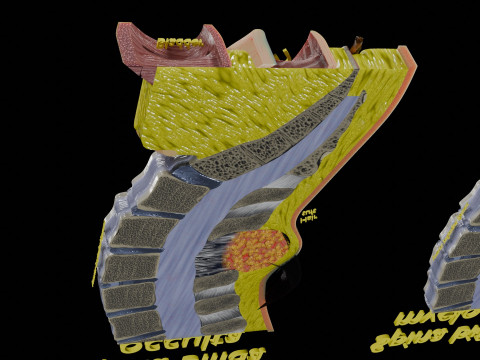

spinal fixation system - titanium bracket. human spine, spinal cord, sacrum and fixation system medically accurate high quality 3d model.

hi-poly 3d model of human spine with internal structure.

you can control polygons by using meshsmooth function . 프린트 준비: 아니오

더 보기hi-poly 3d model of human spine with internal structure.

spine fixation spinal cord screw surgery system anatomy backbone bone brace bracer bracket column disc paralyze titanium treatment vertebra이 아이템에 대한 코멘트 없음.